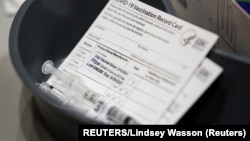

Bela kuća je potvrdila da se razmatra da se od stranih posetilaca zatraži potvrda o vakcinaciji, i na taj način se obnove međunarodna putovanja koja su stopirana ili podrazumevaju restrikcije zbog pandemije.

Džef Zints, koordinator radne grupe Bele kuće za Kovid 19, kazao je da ovakvu mogućnost trenutno razmatra nekoliko federalnih agencija.

Dva otvorena pitanja u vezi sa potvrdama o vakcinaciji su koji bi se dokument smatrao validnim i da li bi se priznavale vakcine koje se ne koriste u SAD. U Americi su odobrene Fajzer, Moderna i Džonson&Džonson vakcina.